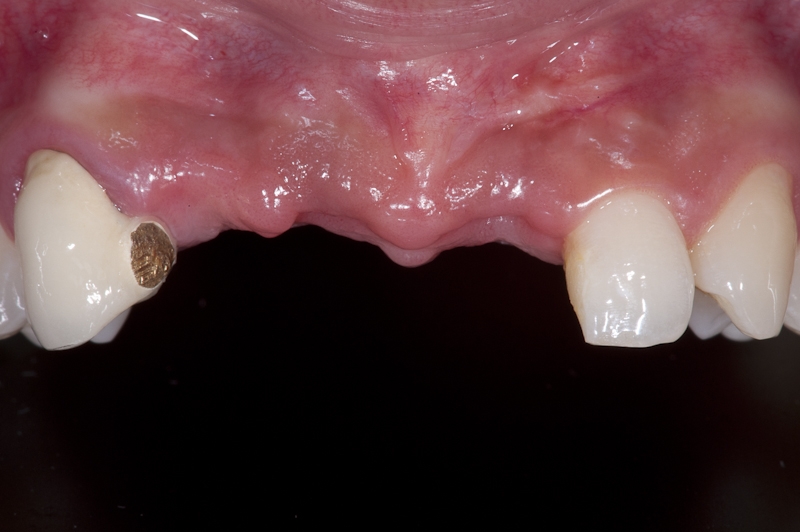

01/17 - Initial situation before surgery. Patient lost central incisors 1 month ago due to endodontic failures